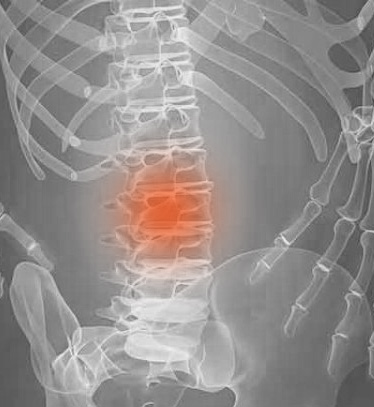

O Canal Lombar Estreito ocorre quando o espaço dentro do canal vertebral se estreita, causando uma compressão das raízes nervosas e da cauda equina na região lombar da coluna. Apesar de ser uma doença relacionada com alterações degenerativas, cuja incidência aumenta com a idade pode, quando tem outras causas, surgir em idades mais jovens.

Exames de imagiologia, como a ressonância magnética ou tomografia computorizada, que permitem obter imagens pormenorizadas da estrutura óssea e dos tecidos moles da coluna vertebral.

Radiografias, para detectar alterações no alinhamento da coluna vertebral e da estrutura óssea.